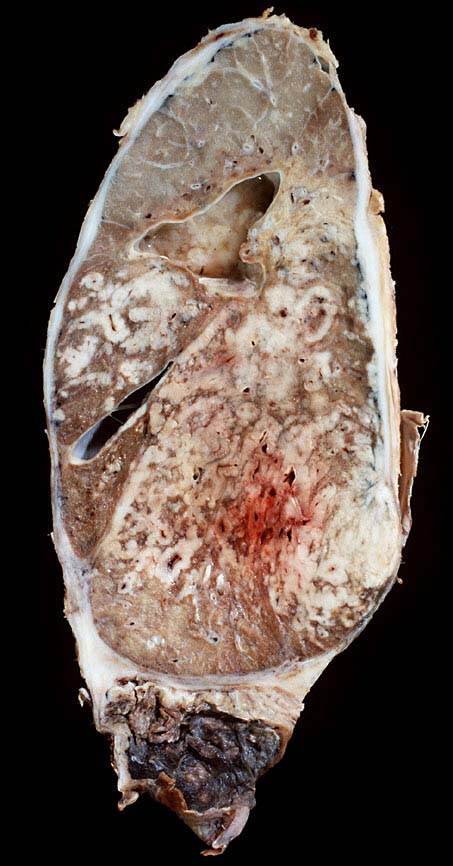

Kleinzellige Karzinome entwickeln sich bevorzugt zentral.

Makroskopie

Befund

Pathologischer Befund